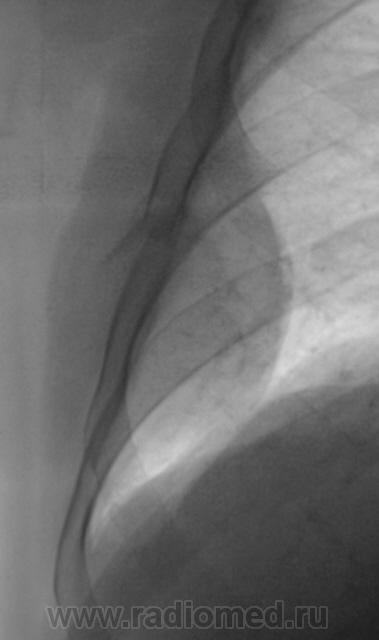

Ну, да массивный мягкотканный компонент есть, но всё же хотелось бы увидеть причинное ребро и в другой (косой) проекции.

Neo ребра (честно говоря, не видел ни разу, поэтому плохо себе представляю) или перелом с гематомой?

Травмы не было. Жалобы на локальные боли, как раз на уровне "того" места...

Начал бы с УЗИ плевральной полости. Тогда круг поиска занчительно бы сократился. Нео, осумкованный плеврит (гидроторакс), посттравматическая гематома. Пациенты не всегда помнят факт травмы!

Конечно после гистологии. Мезотелиома, согласно "бумажке".

Вас смущает диагноз? А ребро резецировали?

Да, ребро резецировали. О мезотелиоме мы конечно думали, но мысль была, что "ноги" процесса из ребра...

Если учитывать проекционные искажения - то протяженность участка поражения 6 ребра не - менее 8 см., хорошо виден "раструб" . В таких случаях обычно либо солитарнаяя миелома, либо метастатическое поражение... А мезотелиома скорее из области фантастики...

А, узловую форму мезателионы с прорастанием в ребро вы не допускаете?

Все контактные прорастания никогда не дают раструба - элемента вздутия, а дают краевые узуры, и при такой длине поражения обязательно было бы прорастание нескольких - хотя бы двух ребер... но чтобы такая локальная мезотелиома поразила одно ребро на таком участке - никогда...